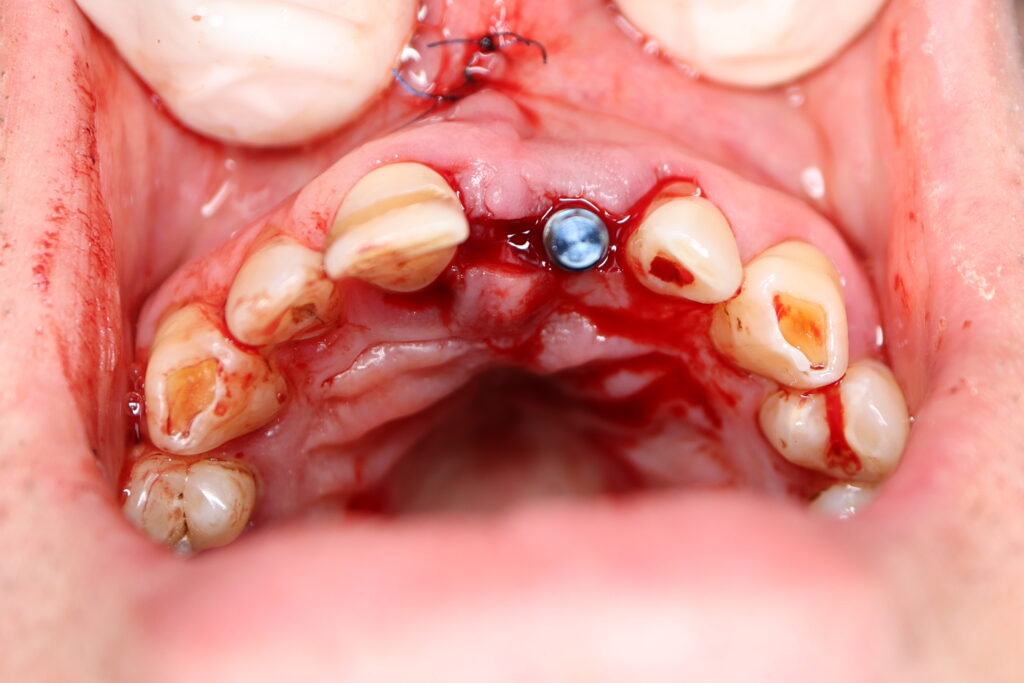

Процесс работы

Что было сделано:

Лечение состояло из двух этапов: хирургический и ортопедический. Длилось 4 месяца.

Были установлены 4 имплантата Straumann BLT. На верхней челюсти в области зуба 2.1 в одно посещение был установлен имплантат и изготовлена временная коронка.

Также в данной области выполнена пластика десны.

хирургический этап

Это фото может содержать тяжелый для восприятия контент